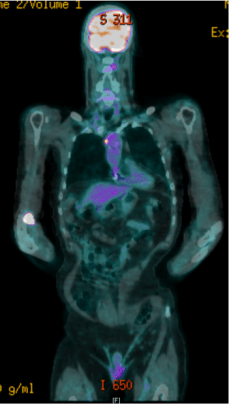

Introduction Pyrexia of unknown origin (PUO) is defined as a temperature greater than 38.3oC on several occasions, accompanied by three weeks of illness and a failure to reach a diagnosis after one week of inpatient investigations [1]. We describe a case of a 72-year-old man with a significant cardiac history and a pacemaker in-situ presented to the emergency department of a district general hospital with sepsis five days after he had his pacemaker unit batteries changed. He had deranged vital signs, productive cough and pyrexia. He had a normal chest plain radiograph (CXR). However, with right basal crackles on auscultation, he was empirically treated for a lower respiratory tract infection (LRTI) with intravenous antibiotics. The patient was discharged but had to be readmitted four times over the span of 4 months due to recurrent pyrexia. Repeated Trans-thoracic (TTE) and Trans-oesophageal (TOE) echocardiograms, and CT neck/thorax/abdomen/pelvis were done however no evidence of infection was found on the scans. A FDG-PET scan was eventually done which showed evidence of pacemaker-lead infection. His pacemaker unit was removed and replaced with a REVEAL device. He improved clinically with no further hospital admission to date.

Methods Routine blood test only showed raised WCC and CRP. Connective tissue disease screen, viral and tumour markers, syphilis serology, and hepatitis screen were negative. Two out of six blood cultures (on separate admissions) done grew Enterobacter cloacae. Repeated CXRs, CT scans and Echocardiograms showed no evidence of collection/infection. A FDG-PET scan was carried out which detected a focus point of increased activity around the pacemaker leads.

Results Enterobacter cloacae is a nosocomial, gram-negative, facultatively anaerobic, rod-shaped bacterium from the Enterobacteriaceae family. It is usually found in the gut normal flora and skin of humans. It can colonise surgical equipment, operative cleaning solutions and heparin solution used to irrigate certain intravascular devices [2]. The surgical equipment used in this patient’s pacemaker battery change may have been colonised with the bacteria which could explain why it was present in the blood cultures. Another explanation would be that it was a skin commensal for the patient. However, to our knowledge, no other cases from the hospitals involved have been identified or reported recently. Unfortunately, when the pacemaker was removed in our patient, the pacemaker leads were not sent for culture and were discarded. The type of PET scan used in this case was the FDG- PET. Hybrid F18- FDG-PET/CT has high sensitivity and relative non-specificity for malignancy, infection and inflammation [3,4]. The subsequent removal of the pacemaker led to the improvement and resolution of symptoms.

Figure 1. FDG-PET scan images showing increased focal activity around pacemaker leads.

Figure 2. CT appearances: no evidence of soft tissue abnormality. There is a small focus of increased activity (SUV-max 7) around the pacemaker leads as they pass from the left brachiocephalic vein into the superior vena cava. Increased activity in the right antecubital fossa correlates to some tissuing at the injection site.